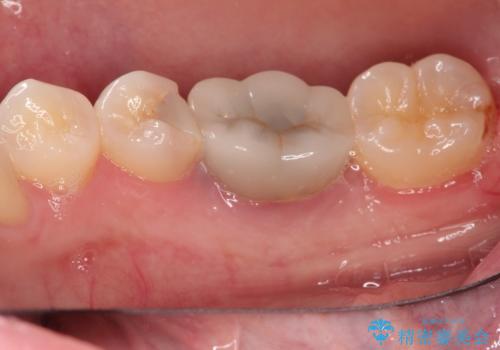

見た目では問題がなさそうでも、レントゲン撮影・診査を行うと状態が悪くなっていることがあります。